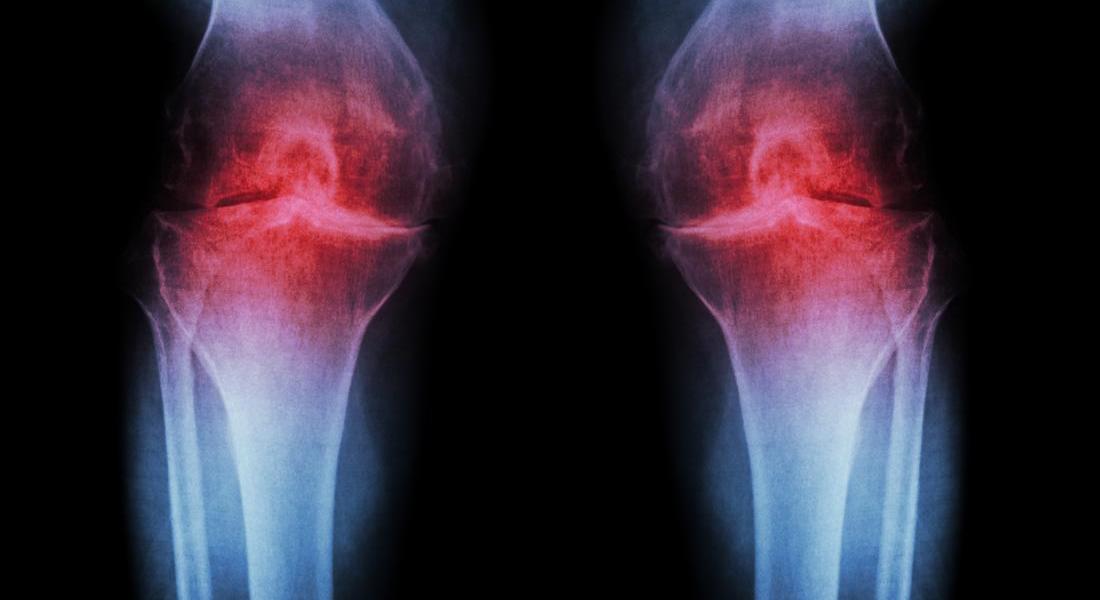

Under normal conditions, articular cartilage is a very stable tissue w

ith almost no new matrix synthesis or breakdown. However, in response to injury, disease or aging, articular chondrocytes begin to break down matrix at a faster rate than they replace it. The result is formation of focal lesions of cartilage loss, known as articular cartilage defects, which eventually expose the underlying bone in large areas of the joint surfaces. These defects prevent smooth gliding motion of the joints and the exposed bone causes intense pain for patients. The end result of these changes is Osteoarthritis.